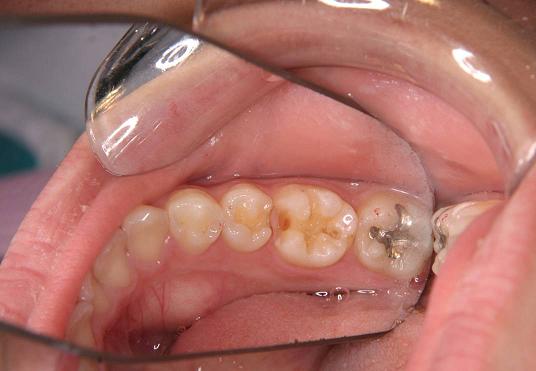

【症例 1】左下5・6番(一部分)2本 (18才,女性)

奥歯の歯の間が2本虫歯で

歯を削った後です

(ミラー像)